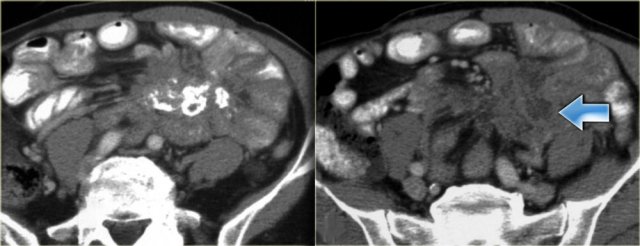

When these peritoneal inclusion cysts become very large, they may extend into the upper abdomen as is seen in the case on the left.

Notice that the left ovary is encircled by the cyst (arrow).

There are also some enhancing septa.

On the left images of a male patient, who presented with a lower abdominal mass.

There is a multi-cystic mass extending from the pelvis along the right paracolic gutter to the upper abdomen.

In a male patient this is a very uncommon diagnosis.

These images look quite similar to images of a pseudomyxoma peritonei which was discussed before.

In peritoneal inclusion cysts however, you will not see scalloping of the surface of the liver.